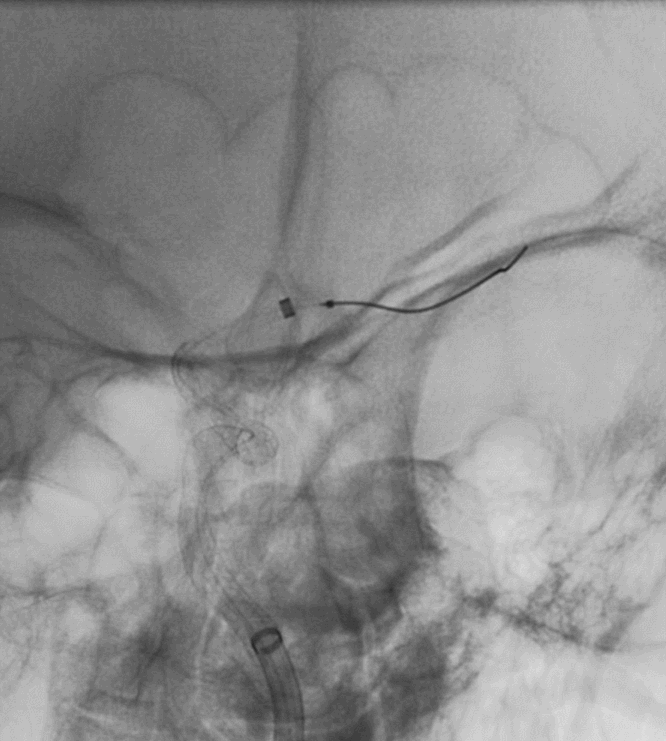

脑血管造影提示右侧颈内动脉颅内段多发动脉瘤(反主动脉弓)

脑血管造影提示右侧颈内动脉颅内段多发动脉瘤

4mm×30mm Streamline